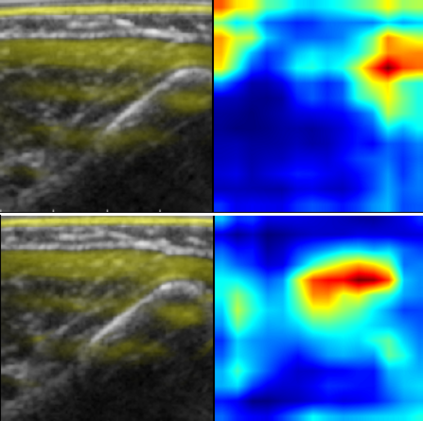

Neuromuscular diseases (NMDs) cause a significant burden for both healthcare systems and society. They can lead to severe progressive muscle weakness, muscle degeneration, contracture, deformity and progressive disability. The NMDs evaluated in this study often manifest in early childhood. As subtypes of disease, e.g. Duchenne Muscular Dystropy (DMD) and Spinal Muscular Atrophy (SMA), are difficult to differentiate at the beginning and worsen quickly, fast and reliable differential diagnosis is crucial. Photoacoustic and ultrasound imaging has shown great potential to visualize and quantify the extent of different diseases. The addition of automatic classification of such image data could further improve standard diagnostic procedures. We compare deep learning-based 2-class and 3-class classifiers based on VGG16 for differentiating healthy from diseased muscular tissue. This work shows promising results with high accuracies above 0.86 for the 3-class problem and can be used as a proof of concept for future approaches for earlier diagnosis and therapeutic monitoring of NMDs.